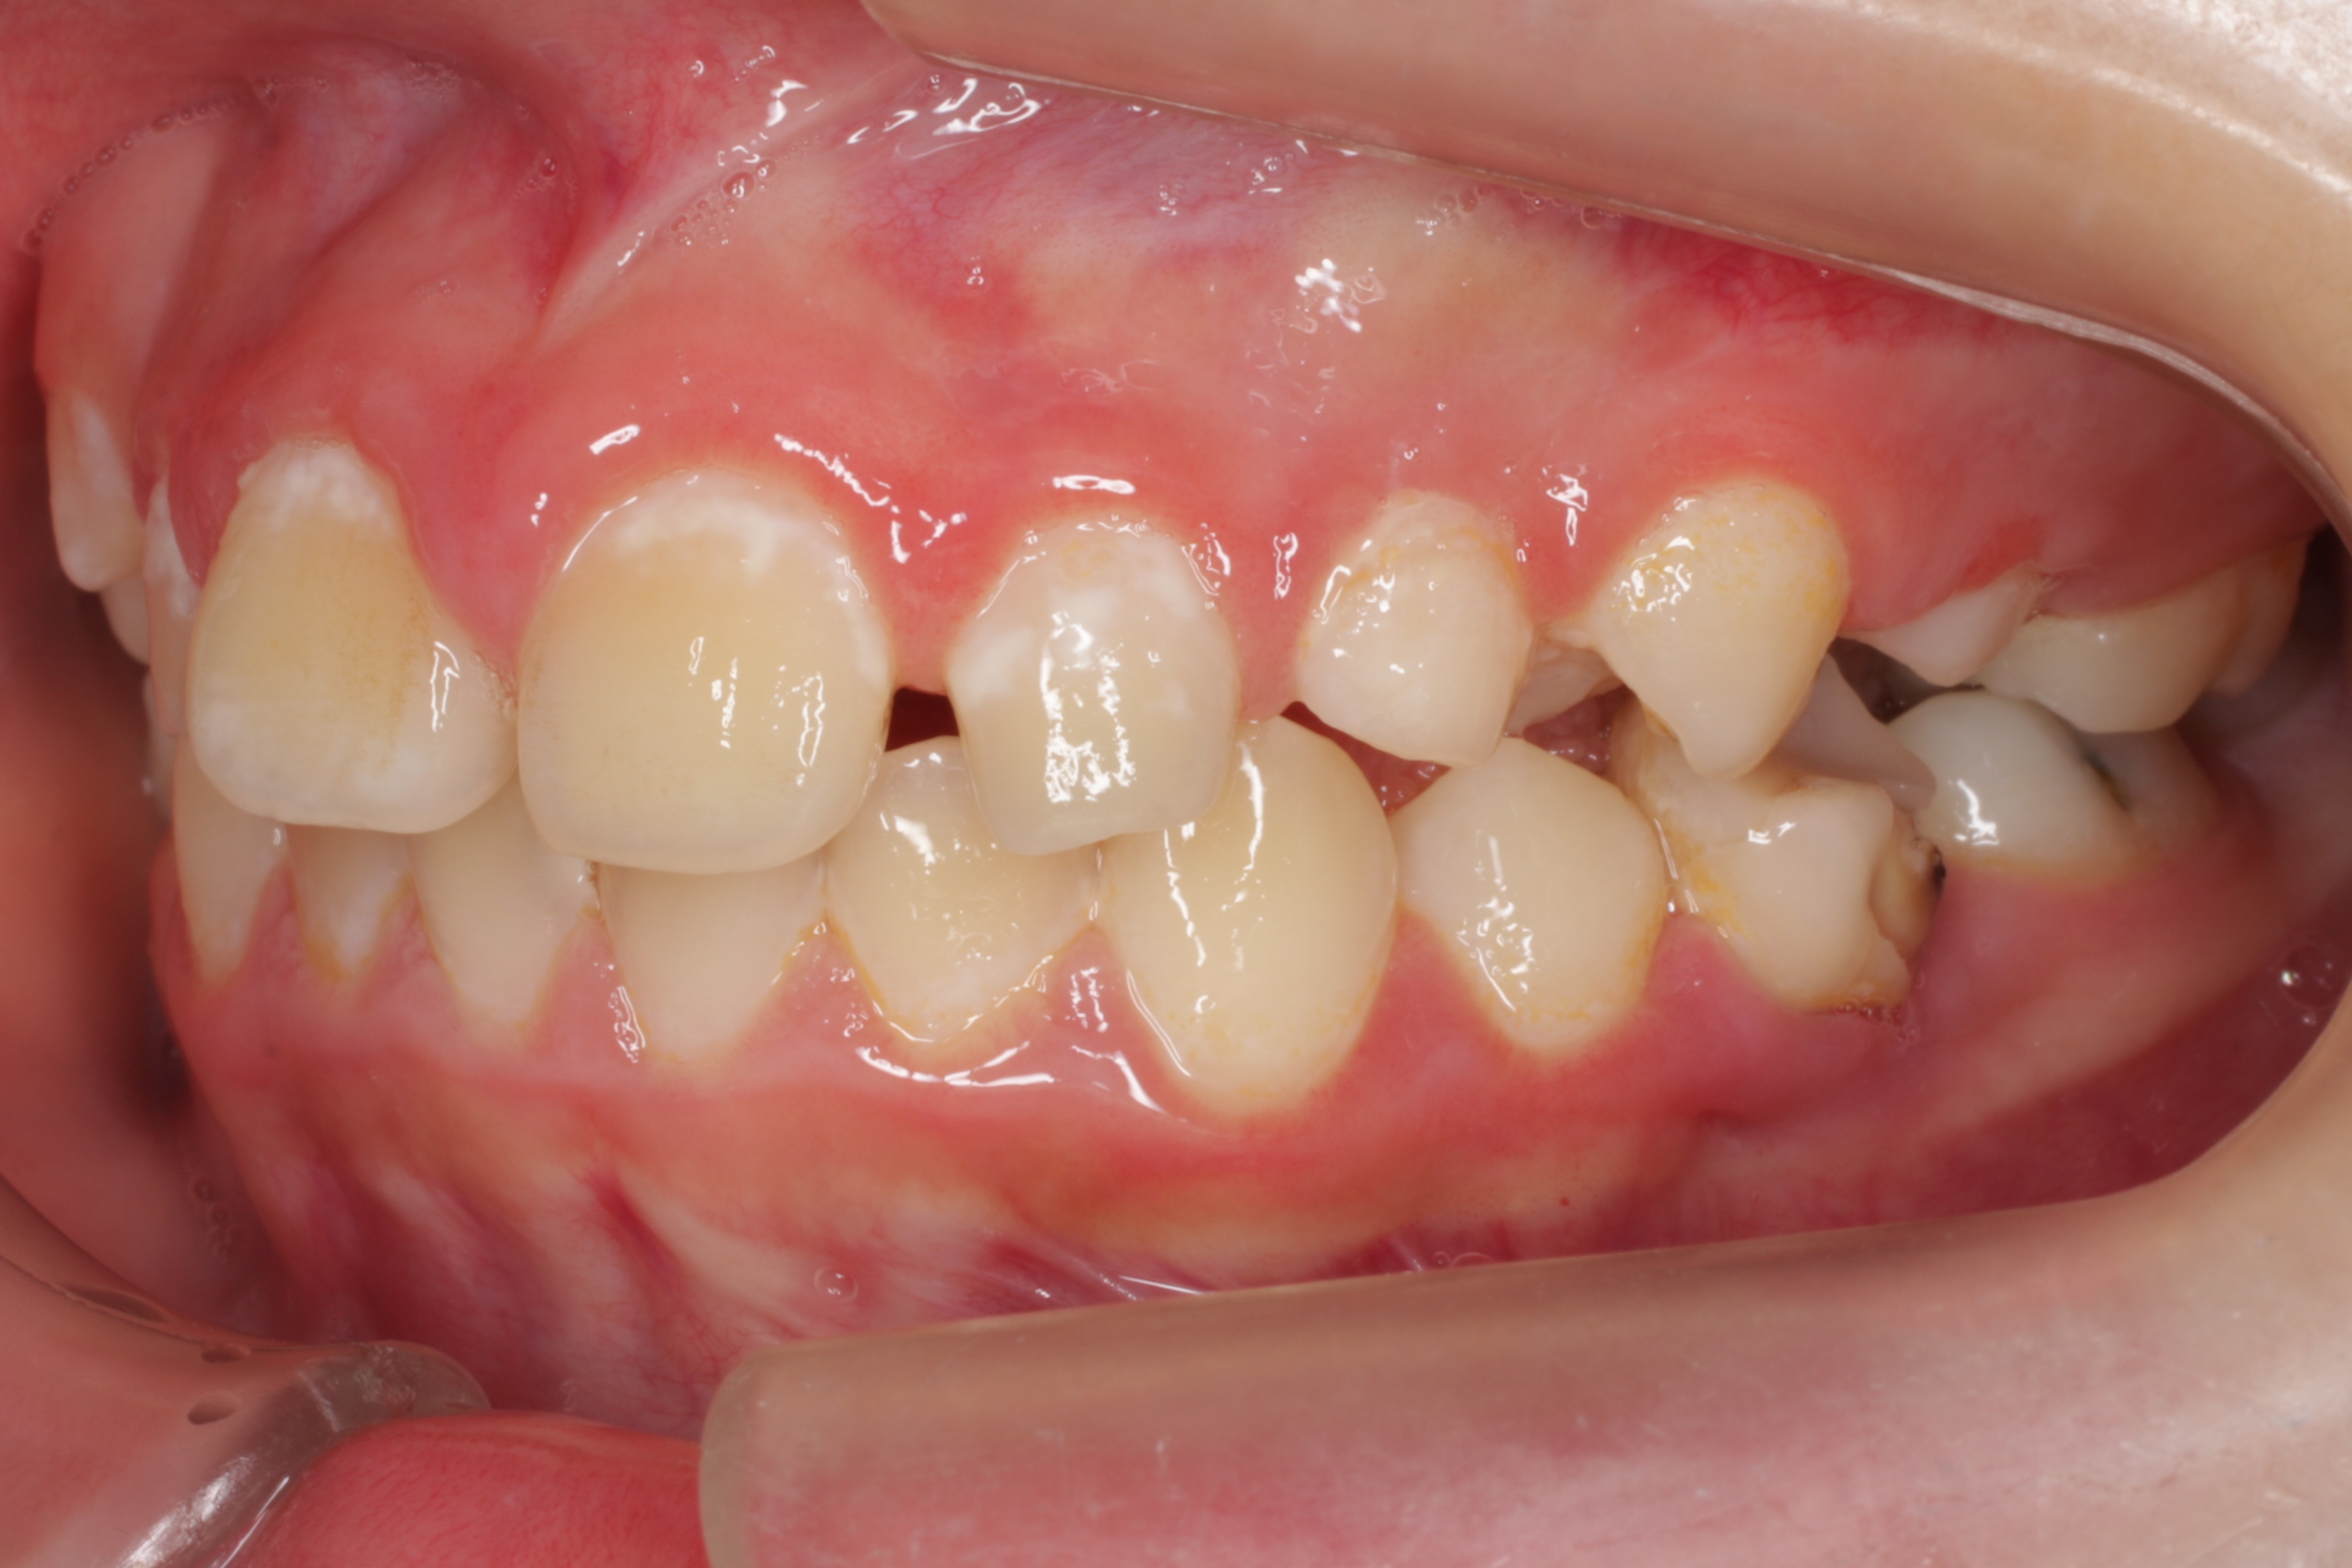

学校健診で虫歯と言われ、来院してくれた子供さんです。とても良い子で、お家の方も感じの良い方です。ただ、気がつくチャンスが無かっただけなのです。歯の大切さと予防歯科の重要性に。

歯科医や学校がもっと予防歯科の普及に頑張らないといけないなと深く反省させられる瞬間です。ごめんなさい。ごめんなさい。

一般的には「何本か虫歯があるので、歯医者に行ってなおしてもらおう」といった感覚なのでしょう。悲しいかな日本ではそれがフツーです。

問題はこの子の家庭に予防歯科の概念と知識が欠如している事なのです。何回も言っているように歯医者に行っても歯は元通りにはなりませんし、修繕が追いつかない程の速度で虫歯ができています。

この子は、これから一生の間に少なくとも100回は歯ぐきに注射をされて、少なくとも300回は通院し、歯を削られたり、神経を抜かれたり、銀歯を入れられたり、そしていつかは歯を抜かれたりするようになります。歯科医師の私にはこの悲しい将来が見えてしまいます。

一日も早く、一人でも多くの方が予防歯科の重要性に気がついて欲しいと思います。そのために私達歯科医療従事者も頑張ります!